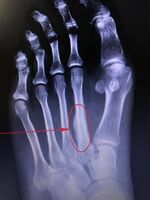

Lisfranc fracture Jacques Lisfranc de St. Martin fracture dislocation of midfoot forced plantar flexion of foot or dropping heavy weight on foot Lisfranc fracture at Who Named It? LisFrancArrow.png